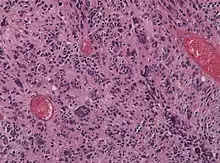

![]() | Tumor giant cell | Malignant neoplasm showing marked anaplasia. Note the marked nuclear pleomorphism, bizarre cells and tumor giant cells. | Category: Histopathology of giant cell tumors | Giant cell tumor |